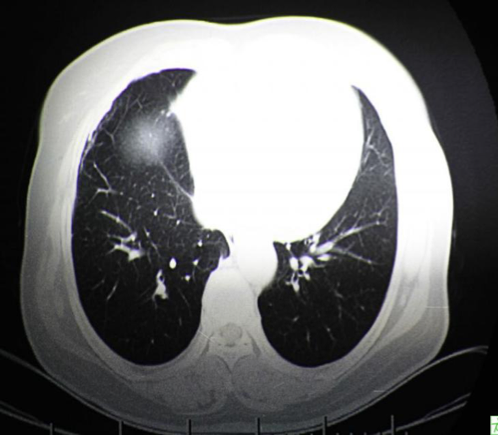

1、肺癌的发病率?

男性肺癌发病率和死亡率均占所有恶性肿瘤的第一位,女性发病率占第二位,死亡率占第二位。

3、肺癌怎么诊断?

胸部X线、胸部CT、纤维支气管镜检查、肿瘤标志物等即可明确诊断。此外,还需完善ECT、细胞学、PET-CT等检查。